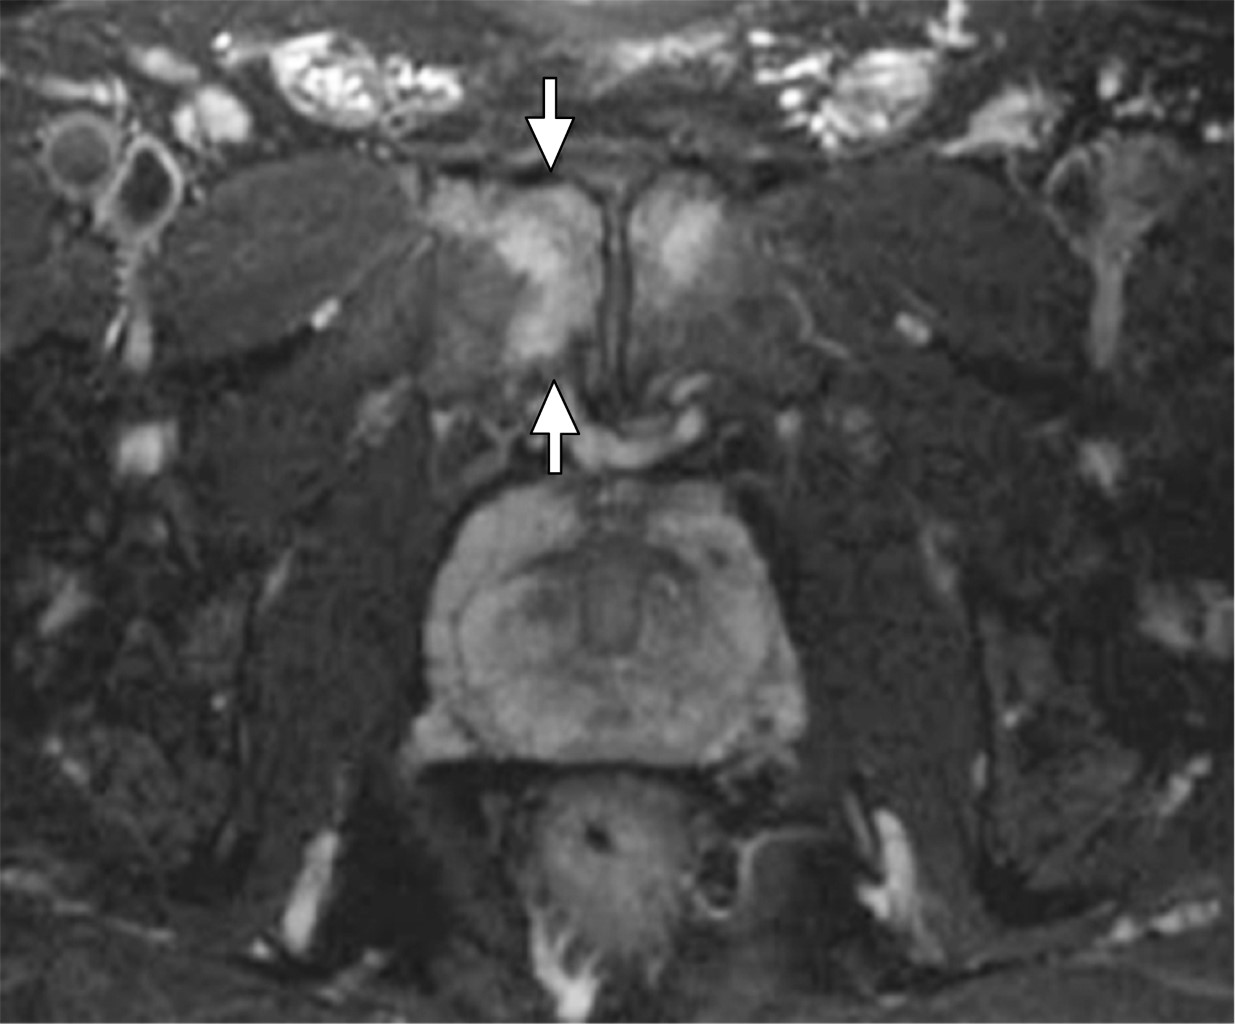

Podemos realizar una primera aproximación diagnóstica solicitando una radiografía de pelvis, con proyecciones anteroposteriores y axiales, por su facilidad y coste a la hora de realizarse. Comúnmente, evidenciaremos esclerosis subcondral, irregularidad de la sínfisis y resorción ósea, en casos avanzados (Figura 1).8 La prueba que mayor información nos va a aportar será la resonancia magnética (RM). Será frecuente encontrarse un edema medular difuso, el cual se extiende desde la superficie subcondral, que a menudo involucra ambas ramas púbicas.9 Además, se suelen encontrar signos de periostitis, irregularidades de las superficiales articulares, erosiones, osteofitos anteriores y posteriores y quistes subcondrales. El signo de la herradura está comúnmente presente (Figura 2). Las uniones miotendinosas se conservan, a menos que haya tendinopatía coexistente.9

Figura 2